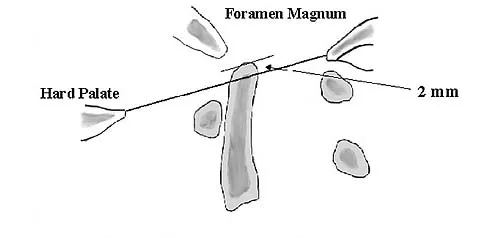

Figures 20a through 20d show the radiographs and MRI scans of a 59-year-old woman who has had symptoms consistent with progressive neurogenic claudication and back pain for the past 9 months. In the last 6 months, nonsurgical management consisting of nonsteroidal anti-inflammatory drugs, physical therapy, and a series of epidural steroid injections have been used; however the injections, while beneficial, have provided only temporary relief of her symptoms. What is the most appropriate management at this time?

Explanation